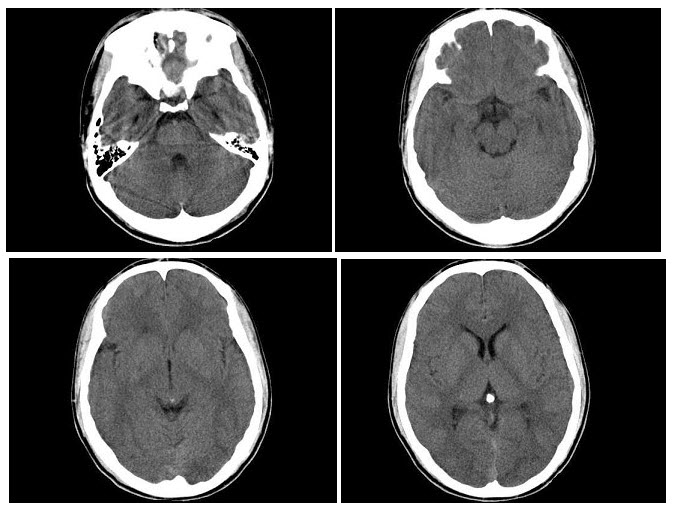

10、单项选择题

这个急诊患者剧烈上腹痛,结合图像,最可能的诊断是()

E.椎体边缘及椎小关节骨质增生

17、单项选择题

B.肿瘤常有纤维性假包膜

C.平扫软组组密度

A.黑质

B.脑干